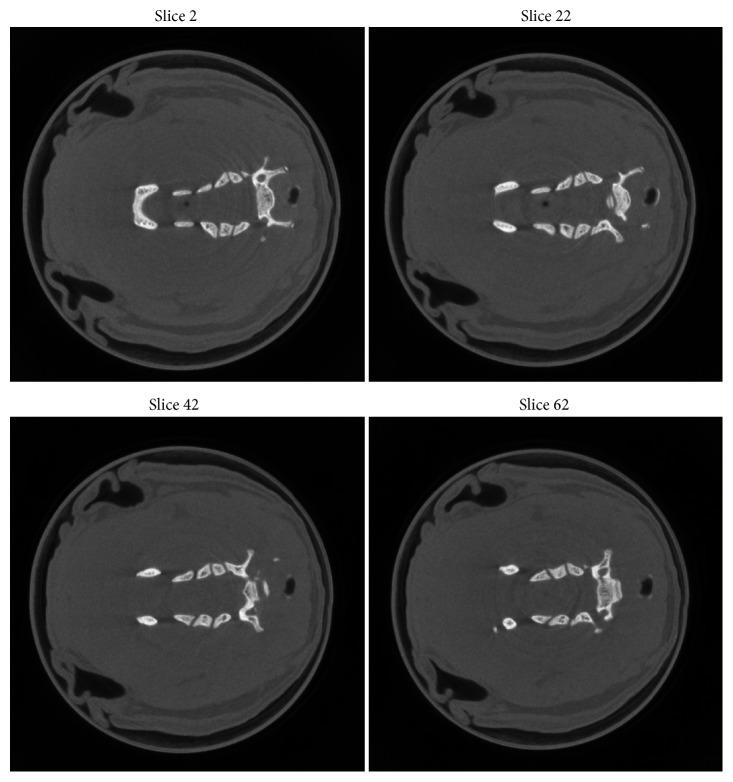

Photon-counting detector (PCD) can identify absorption features in the multiple ranges of photon energies, which has a great potential in material discrimination. In this paper, we focused on in vivo dual-energy CT imaging to characterize different biomedical compositions. The precision of material decomposition in post-reconstruction space depends on the quality of reconstructed CT images; we used the locally linear embedding (LLE) based online geometric calibration method and GPU-based reconstruction toolbox to reconstruct high-quality CT images. Then, we performed the real experiment and studied materials decomposition with basis material model to discriminate soft tissue and cortical bone of small animal. Finally, the experimental results demonstrated that the proposed method could reconstruct small animal CT images with more slim structures and details, and improve the precision of materials decomposition in dual-energy CT imaging.

光子计数探测器(PCD)可以识别光子能量的多个范围内的吸收特征,在物质鉴别方面具有很大的潜力。在本文中,我们专注于体内双能 CT 成像,以描述不同的生物医学成分。在重建后空间中的材料分解精度取决于重建 CT 图像的质量;我们使用基于局部线性嵌入(LLE)的在线几何校准方法和基于 GPU 的重建工具包来重建高质量的 CT 图像。然后,我们进行了实际实验,使用基础物质模型对材料分解进行了研究,以区分小动物的软组织和皮质骨。最后,实验结果表明,所提出的方法可以重建具有更纤细结构和细节的小动物 CT 图像,并提高双能 CT 成像中材料分解的精度。